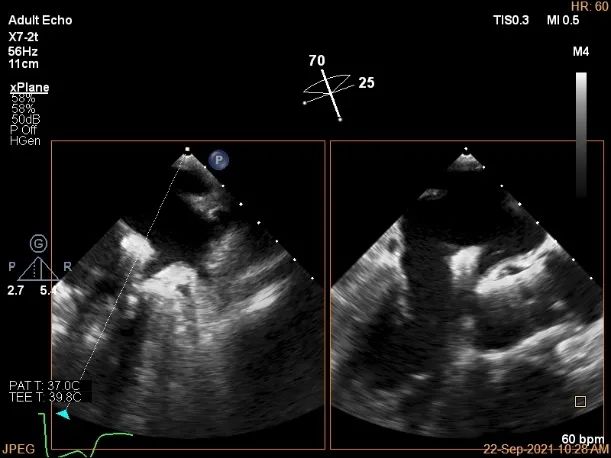

术中超声

P2区脱垂,宽14.8mm,Gap:3.3mm

3D-color,返流重度,3+级